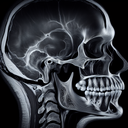

МРТ скронево-нижньощелепного суглоба

Магнітно-резонансна томографія (МРТ) скронево-нижньощелепного суглоба – це неінвазивне дослідження, яке дозволяє детально оцінити стан суглоба, м’яких тканин, дисків та інших структур. ### Коли призначають: - Біль або дискомфорт у щелепі - Труднощі з рухливістю або блокування щелепи - Підозра на дисфункцію або патології суглоба ### Переваги: - Висока точність і деталізація зображень - Безпека, оскільки немає іонізуючого випромінювання ### Підготовка: - Зазвичай спеціальної підготовки не потрібно, але пацієнта можуть попросити зняти металеві прикраси. - Інформування лікаря про наявність імплантів або протезів, які можуть бути несумісними з МРТ...